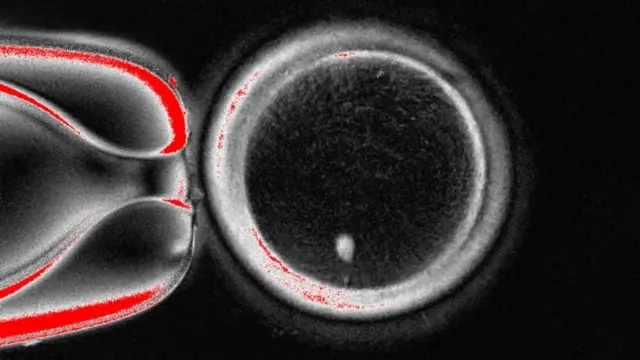

บรรยายรูป:วงกลมขนาดใหญ่นี้คือไข่ที่ถูกมองผ่านกล้องจุลทรรศน์

จุดสีขาวบริเวณด้านล่างคือสารพันธุกรรมที่ถูกย้ายจากเซลล์ผิวหนังมาใส่ไว้

โดยปกติแล้วมนุษย์จะสืบทอดดีเอ็นเอจากพ่อและแม่มาคนละ 23 แท่ง จนรวมกันเป็น 46 แท่ง ซึ่งในไข่ใบนี้มีครบอยู่แล้ว